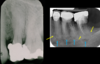

Q

what is this superimposition?

A

maxillary antrum

17

soft tissue of the nose

18

zygomatic buttress

19

mental foramen